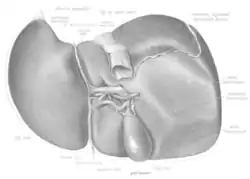

The liver, viewed from below, surface showing four lobes and the impressions

The liver is grossly divided into two parts when viewed from above – a right and a left lobe – and four parts when viewed from below (left, right, caudate, and quadrate lobes).[14]

The falciform ligament makes a superficial division of the liver into a left and right lobe. From below, the two additional lobes are located between the right and left lobes, one in front of the other. A line can be imagined running from the left of the vena cava and all the way forward to divide the liver and gallbladder into two halves.[15] This line is called Cantlie's line.[16]